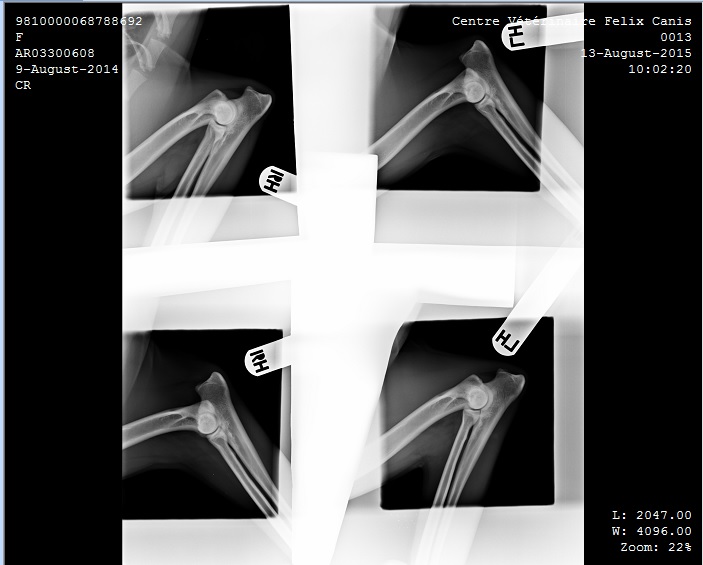

Alexa 3 Published August 14, 2015 at 703 × 565 in Hip and Elbow X-ray’s Keith and Alexa ← Previous Alexa